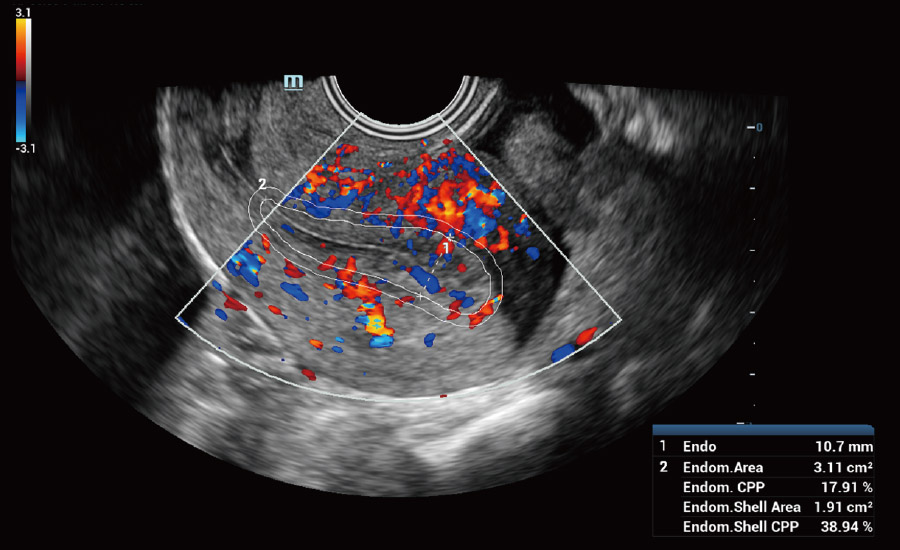

UMA (Ultra-Micro Angiography)

The innovative technology breaks the bottlenecks of traditional Doppler imaging. With ultra-high spatial resolution and flow sensitivity, it allows detecting super-subtle and super-slow flow perfusions, thereby extending the clinical application of qualitative and quantitative ultrasound evaluation in fetal brain, kidney, placenta, endometrium, ovary, etc.

UMA - uterine and endometrial flow